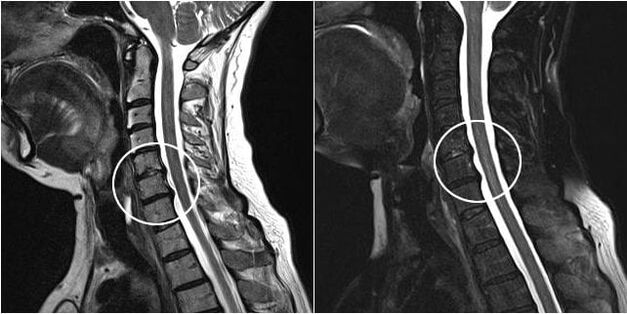

As the intervertebral discs and vertebrae deform, the patient's condition worsens.The course of osteochondrosis is complicated by neurogenic symptoms caused by compression by osteophytes or hernial protrusion of spinal roots and vertebral artery.Headaches, dizziness, changes in blood pressure appear, and the sharpness of vision and hearing decreases.

Surgical intervention

Indications for surgical intervention include ineffectiveness of conservative treatment, as well as complications of cervical osteochondrosis, for example, discogenic myelopathy, vertebral artery syndrome and radicular syndrome.To decompress the spinal cord, blood vessels and spinal roots, the following operations are performed:

During surgery, bone fragments and ligaments can be removed and the intervertebral discs can be removed completely or partially.For small herniated protrusions, laser vaporization of the disc core is often performed.

After removal of the vertebral structures, stabilization of the motion segments of the spine is often required by spinal fusion or installation of bone and dermal autografts.